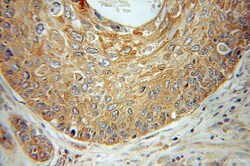

11091-1-AP IHC

Full details

Method: Other validation